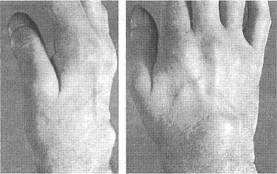

Обычно ревматоидный артрит начинается с симметричного полиартрита периферических суставов (рис.1), что проявляется их припухлостью, болезненностью и скованностью, причем последняя может поражать большее количество суставов, чем первые два симптома. Характерным для ревматоидного артрита является вовлечение проксимальных межфаланговых, пястно-фаланговых суставов и лучезапястных суставов кистей. Дистальные межфаланговые суставы, пястно-фаланговый сустав I пальца и проксимальный межфаланговый сустав V пальца кисти считаются "суставами исключения" так как в большинстве случаев остаются интактными в дебюте болезни, однако могут вовлекаться в процесс при прогрессировании ревматоидного артрита.

Припухлость пястно-фаланговых и проксимальных межфаланговых суставов кистис веретенообразной де фигурацией последних, ассоциирующаяся с утренней скованностью, затруднением сжатия кисти в кулак, снижением кистевой силы и болезненностью при пальпации (см. рис.1).

Одним из ранних симптомов ревматоидного артрита является уменьшение массы межкостных мышц на тыле кистей, связанное со снижением их функциональной активности.

Рис.1. Кисты больного с ранним ревматоидным артритом